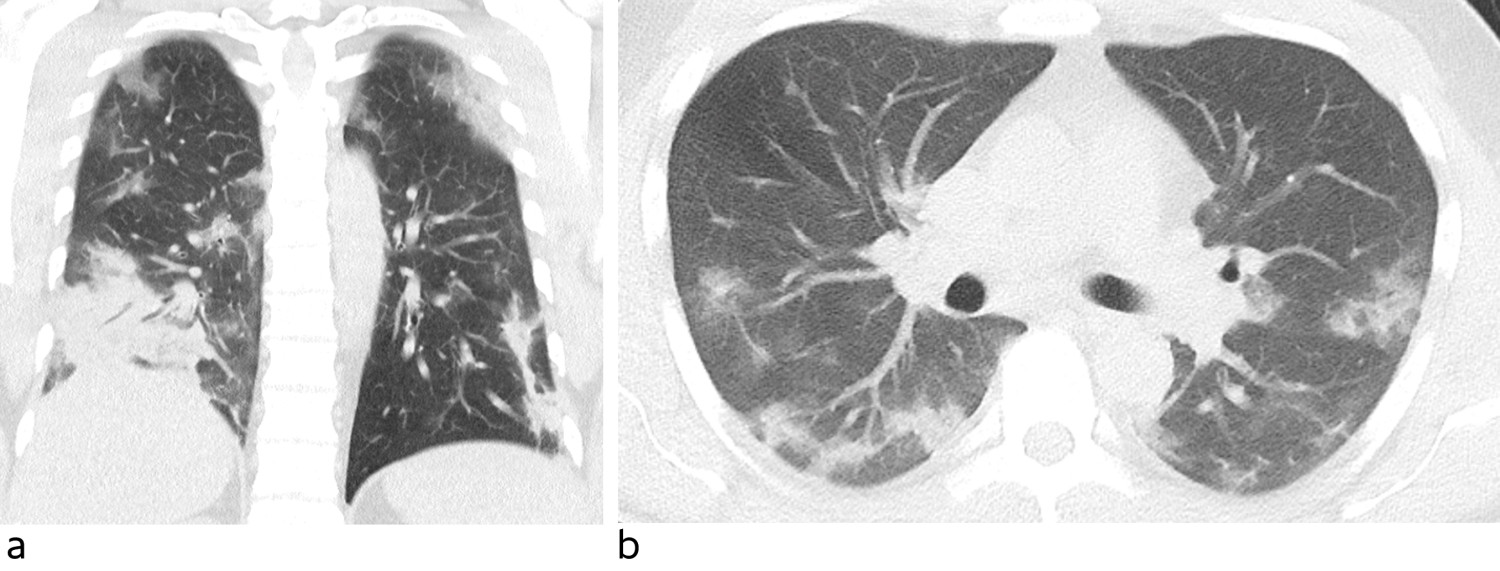

Blodprøver viste hemoglobin (Hb) 12,3 g/dl (13–17), normale leukocytter med normal differensialtelling, senkningsreaksjon (SR) 36 mm (< 13), C-reaktivt protein (CRP) 121 mg/l (< 5), albumin 33 g/l (39–50), laktatdehydrogenase (LD) 349 U/l (105–205), kreatinkinase (CK) 537 U/l (50–400), aspartataminotransferase (ASAT) 47 U/l (15–45) og ferritin 1 192 µg/l (15–350). CT thorax viste rikelig med diffust avgrensede mattglassfortetninger i alle lungelapper, avvekslende med normalt lungeparenkym (figur 1). Apikale forandringer var mest markert perifert. I tillegg var det en konsolidert fortetning basodorsalt i høyre underlapp. Fem og syv dager etter symptomdebut ble det tatt nasofarynksprøve for sars-CoV-2, som ble analysert med polymerasekjedereaksjonstest (PCR). Begge prøvene var negative.

Bronkoskopi med bronkolalveolær skylling er en aeorosolgenererende prosedyre. Ettersom man mistenker at denne prosedyren øker smitterisikoen for personalet, medfører den strengere krav til bruk av smittevernutstyr (7). Indikasjonen må vurderes nøye opp mot gevinst. I vår kasuistikk var det viktig med svar fordi pasienten tilhørte et skipsmannskap og ønsket seg til hjemlandet. I andre situasjoner kan smitterisikoen for personalet og ubehaget det påfører pasienten overgå viktigheten av å utføre prosedyren. Man kan da velge å heller isolere pasienten på bakgrunn av andre funn som gir sterk mistanke om covid-19. Pasienten hadde reiseanamnese som gav mistanke om smitteeksponering samt symptomer (7) og funn ved CT thorax som var forenlig med covid-19. CT-funn har vist seg å ha høy sensitivitet for påvisning av covid-19, opp mot 95 %. Spesifisiteten er dog lav, da andre virus og atypiske infeksjoner kan gi lignende bilde (4, 8, 9). Foruten høyt ferritinnivå ble det kun sett uspesifikke milde avvik på blodprøvene. Vedvarende høyt ferritinnivå har i retrospektive studier vist seg å være et dårlig prognostisk tegn hos covid-19-pasienter (10).